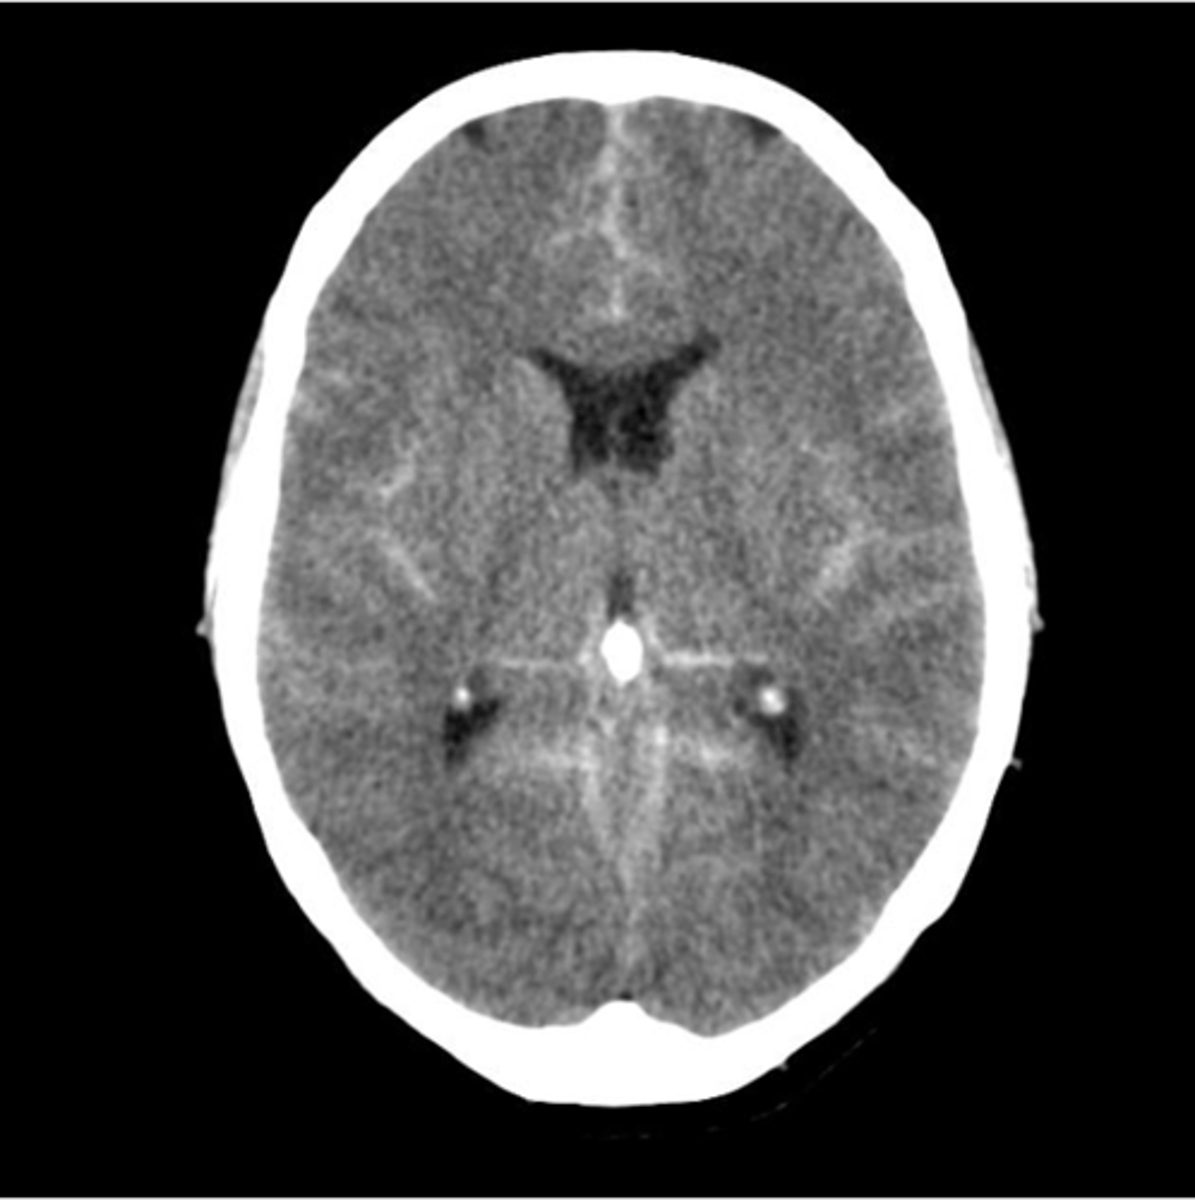

CT w/o contrast can help identify

intracranial bleeding, stroke (ischemic or hemorrhagic), brain/spine tumors, fractures, spinal stenosis

subarachnoid hemorrhage

more diffuse presentation

intracerebral hemorrhage

typically not trauma related; can often come from a ruptured AVM from uncontrolled HTN

ischemic brain injury